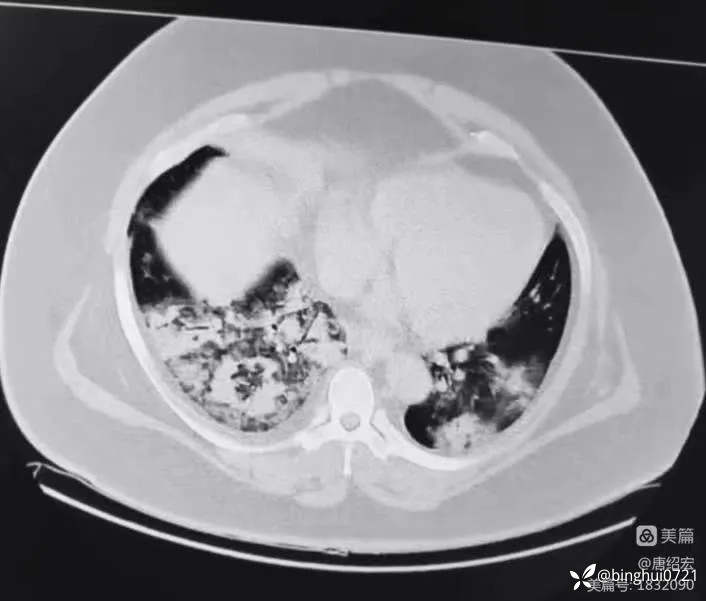

军团菌肺炎的典型CT表现及治疗

男,36 岁,主诉间断发热 1 周,咳嗽伴气短 3 天。入院CT如下:

军团菌肺炎

行肺泡灌洗液 NGS:嗜肺军团菌 3262 条,咽峡炎链球菌 20 条(考虑定植),金葡菌 10 条(考虑鼻咽部向下污染)。